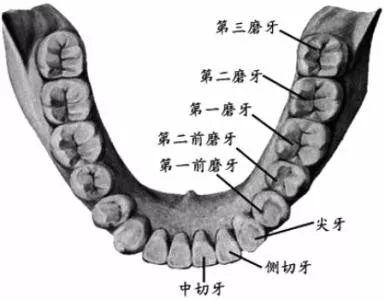

智齒,學名三大臼(jiù)齒,又叫做第三磨牙。

雖然叫做智齒,但其實和智商毫無關系...只是一般在 18 歲后長出來,正處于人類智力發(fā)育的鼎盛期而得名(小時候看鄭淵潔的《智齒》,一直對自己沒有長智齒而耿耿于懷,現(xiàn)在,悔之晚矣...)。

人類在進化過程中,進食的食物是越來越精細,頜骨(就是你的下巴)越來越短,但牙齒不會減少,有的牙齒就沒有空間長出來。嚴肅的推斷出「智齒長不好,說明你臉小」(強行安慰一波長阻生智齒的人)...